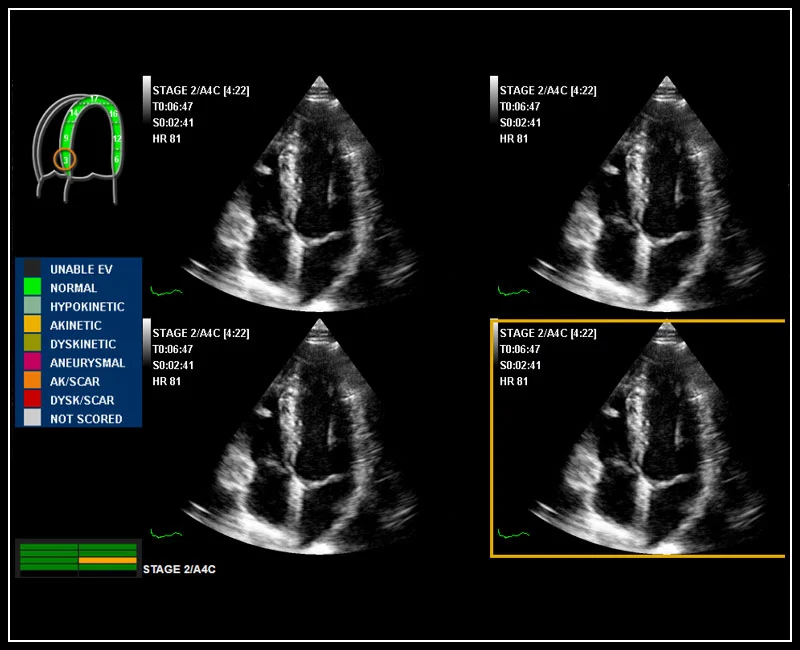

MyLab™X5 - Stress echo

MyLab™X5 - Stress echo